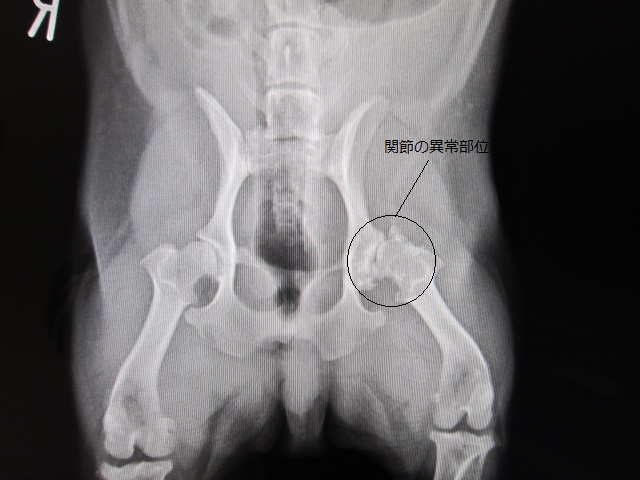

術前

術前のレントゲンです。

右の股関節と比較すると一目瞭然です。